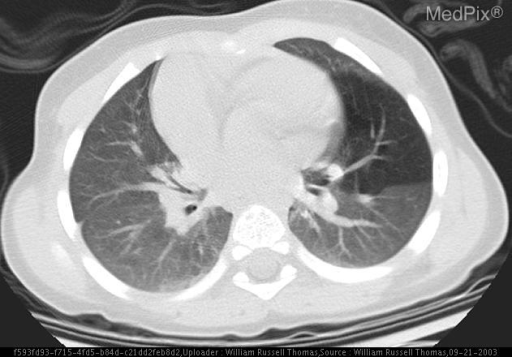

A wide variety of typical and atypical CT abnormalities have been reported for COVID-19 patients in various studies [58, 59]. So, we tested our models on external CT images extracted from these two publications as they feature typical findings of COVID-19 pneumonia marked by specialists. In order to make sure that not any of the extracted images are unintentionally included in our datasets, specifically the COVID19-CT dataset, we use the model trained on the SARS-CoV-2 dataset. First, the InceptionV3 model is employed to classify the extracted CT images. The model is able to correctly classify the given CT images as COVID-19. Second, in order to interpret the model’s generalization capabilities, we apply the Grad-CAM technique to visualize the regions of abnormalities that are considered. By assessing the different CT images in Figure 15, we can see that the model accurately localizes the disease-related regions. Even more interesting is the fact that the model ignores any specific marks in the images like letters and only localizes the COVID-19 related regions. These visual explanations show the success of our models to learn relevant, generic visual features related to COVID-19 and are capable to correctly classify CT images outside the datasets on which they are trained.

Figure 16 shows various CT scans where only one lung is visible. The CT scans are also extracted from the paper [58] and show different CT manifestations of COVID-19 pneumonia marked by red squares. The InceptionV3 model is capable to classify them correctly as COVID-19, although it is trained on CT scans where the entire lung is visible. Intriguingly, when applying Grad-CAM we can see that all regions of abnormalities are accurately localized. This also proves the potential of our model to detect COVID-19 abnormalities in CT images outside the dataset used for training.